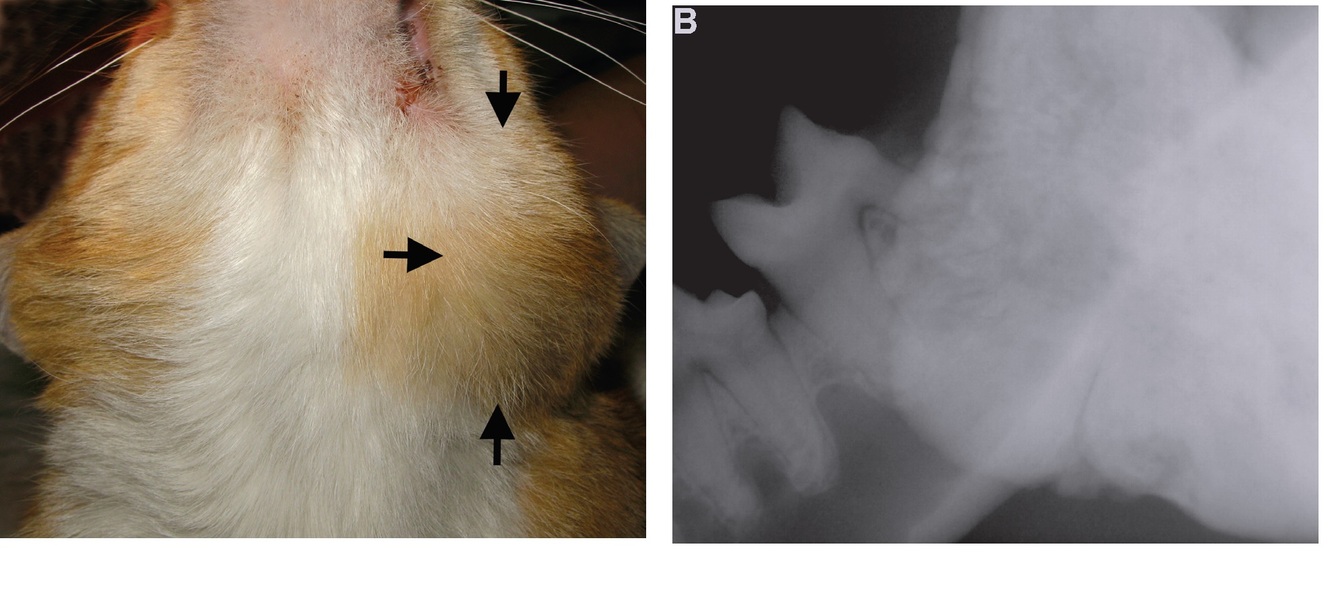

What would be differnetials for this mass, and radiographic appearance?

developmental, neoplastic, and inflammatory conditions.

neoplasia such as squamous cell carcinoma, osteoma and other

bone tumors, and osteitis or osteomyelitis